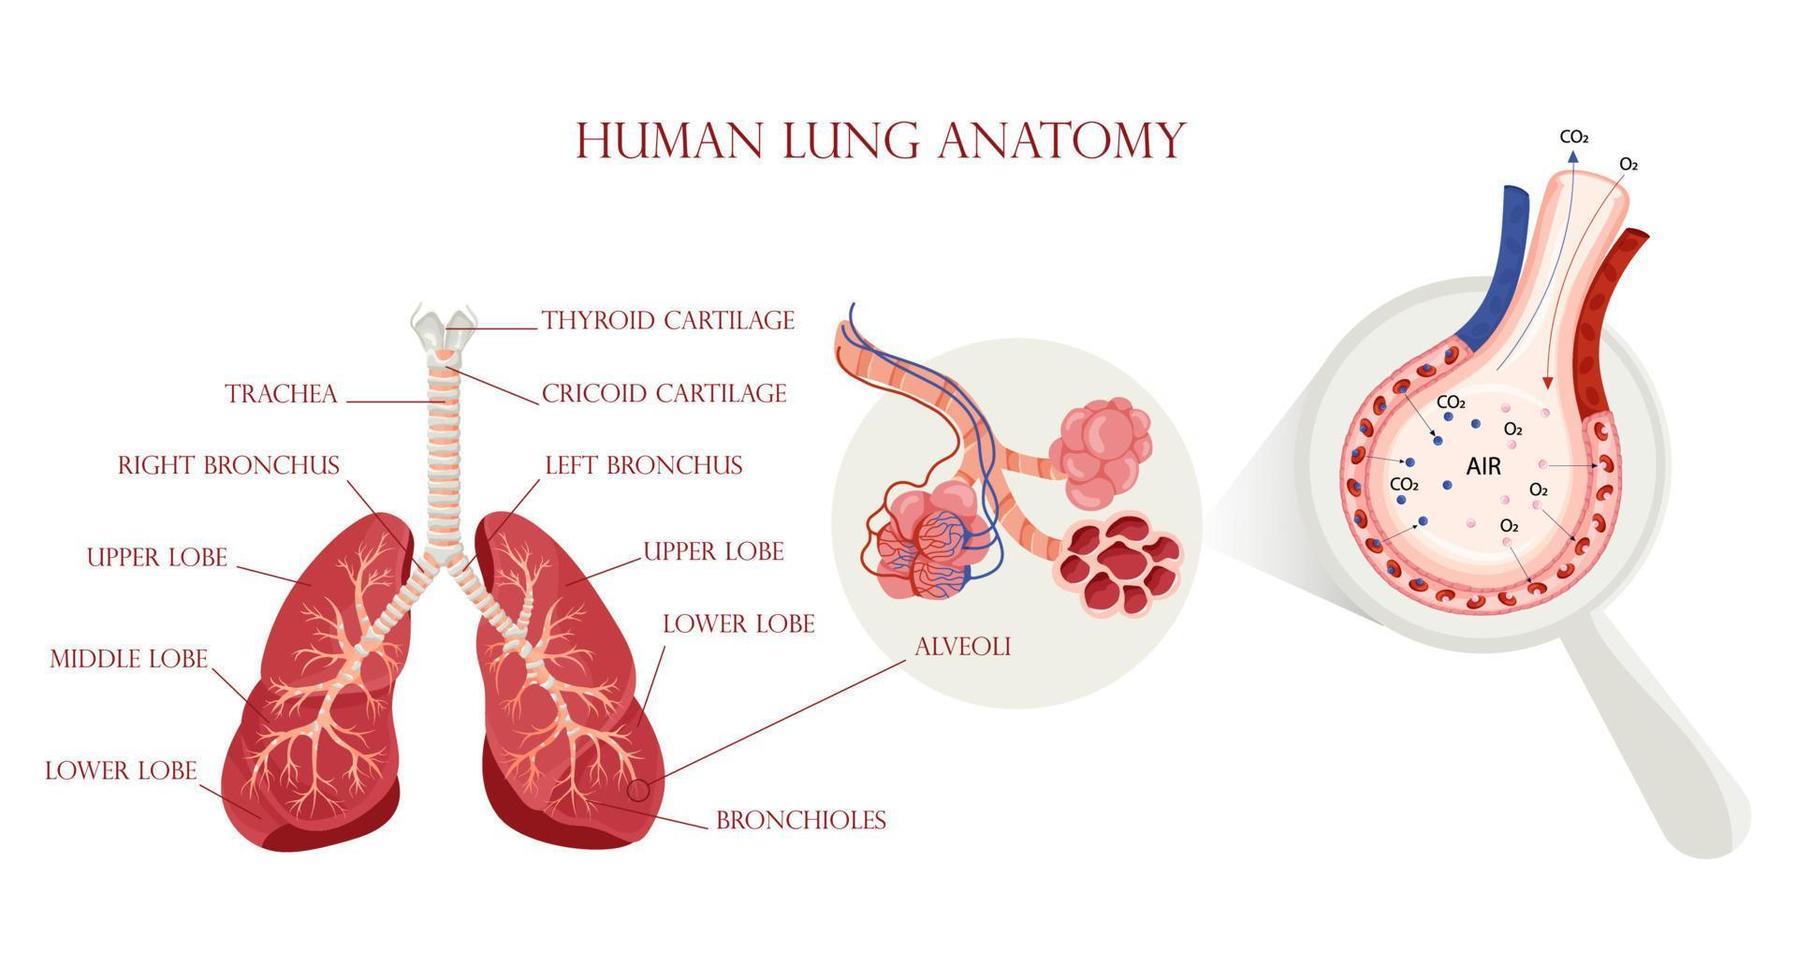

Lung Anatomy, Alveoli Structure And Gas Exchange Scheme 16069886 Vector

www.vecteezy.com

www.vecteezy.com

Premium Vector | Lung Anatomy Alveoli Structure And Gas Exchange Scheme

www.freepik.com

www.freepik.com

Lung Anatomy, Alveoli Structure And Gas Exchange Scheme 16069886 Vector

www.vecteezy.com

www.vecteezy.com